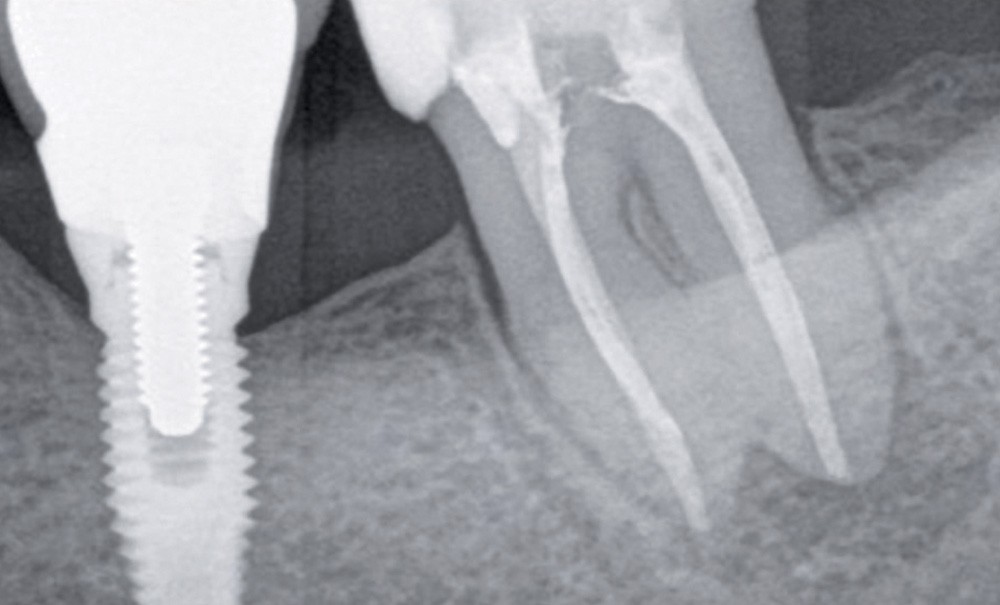

Après l’identification de la maladie (diagnostic) et la prévision de son succès dans le temps (pronostic), la question de la conservation des dents parodontalement compromises se pose et un traitement parodontal peut être envisagé. Une dent est considérée parodontalement compromise si elle présente une perte osseuse comprise entre 60 et 80% de sa hauteur radiculaire. Cependant, la perte osseuse radiologique n’est pas une indication absolue à l’avulsion (fig. 1). Grâce au traitement parodontal et à un suivi régulier, ces dents peuvent être maintenues avec un taux de survie de 93 % à dix ans [2, 8, 9]. Ce taux de survie se rapproche de celui des implants chez un patient aux antécédents de parodontite modérée [10].

1. Suivi parodontal à 7 ans d’une dent parodontalement compromise. Patient de 36 ans, diabétique…